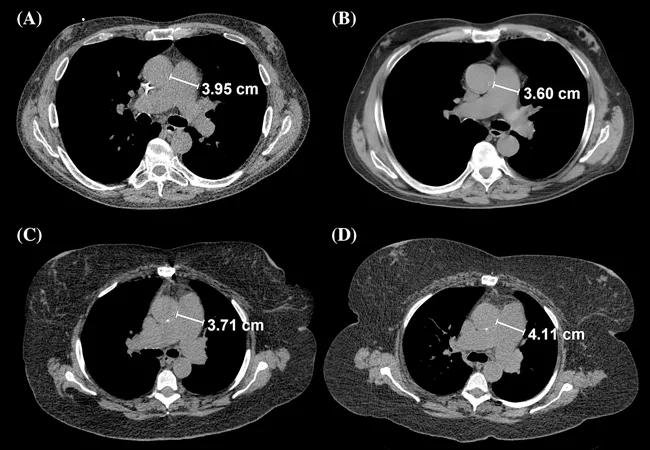

Feature image: Main PA diameter measurement during first and second CT scans of the chest. Panels (A) and (B) correspond to a PAH patient in whom the main PA diameter decreased by 3.5 mm, while panels (C) and (D) showed the axial CT cuts of another PAH patients in whom the main PA diameter increased by 4 mm during follow‐up. Originally published in Respirology.

They found that the main PA diameter increased by at least 1 mm in 40 percent of the patients after 12-month follow up. Overall their data show that time between CT scans was directly associated with the increase in PA diameter. When adjusted by time between scans and difference in slice thickness, three variables were associated with a more pronounced mean PA diameter: a higher PA pulse pressure and lower PA compliance during right heart catheterization, worse RV function on the echocardiograms performed close to the first and second CT scans andhigher right ventricular systolic pressure (RVSP). A decline in the six-minute walk test was also associated with PA dilation.

The researchers found that main PA diameter at baseline was a significant predictor of mortality, when adjusted for difference in time and slice thickness between CT scans, age, gender and PVR. The change in main PA diameter over time was also a significant predictor of mortality when adjusting for the same factors or when adding the diameter of the main PA at baseline, origin of PAH or time from the diagnostic right heart catheterization and initial CT scan of the chest.

“We found that for every 1 mm expansion in the main pulmonary artery, there was a 28 percent increase in mortality,” Dr. Tonelli says.

Change in PA area significantly impacted survival. The median follow-up was 33 months, during which 53 patients (46.9 percent) died and six were censored due to lung transplant. Survival at one and two years was 65 percent and 61 percent, respectively. However, the changes in other determinations such as main PA/Ao diameter ratio, right PA diameter and left PA diameter, were not significant predictors of survival when adjusted for similar variables as used in previous analyses.